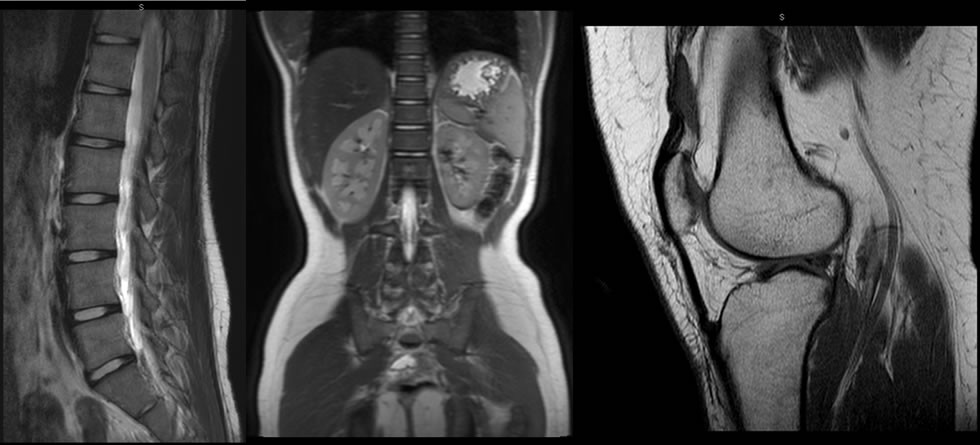

Interpretación de Estudios de Tomografía Multicorte

La interpretación de estos estudios es realizado en estaciones de trabajo que funcionan bajo una plataforma basada en...

Leer más -